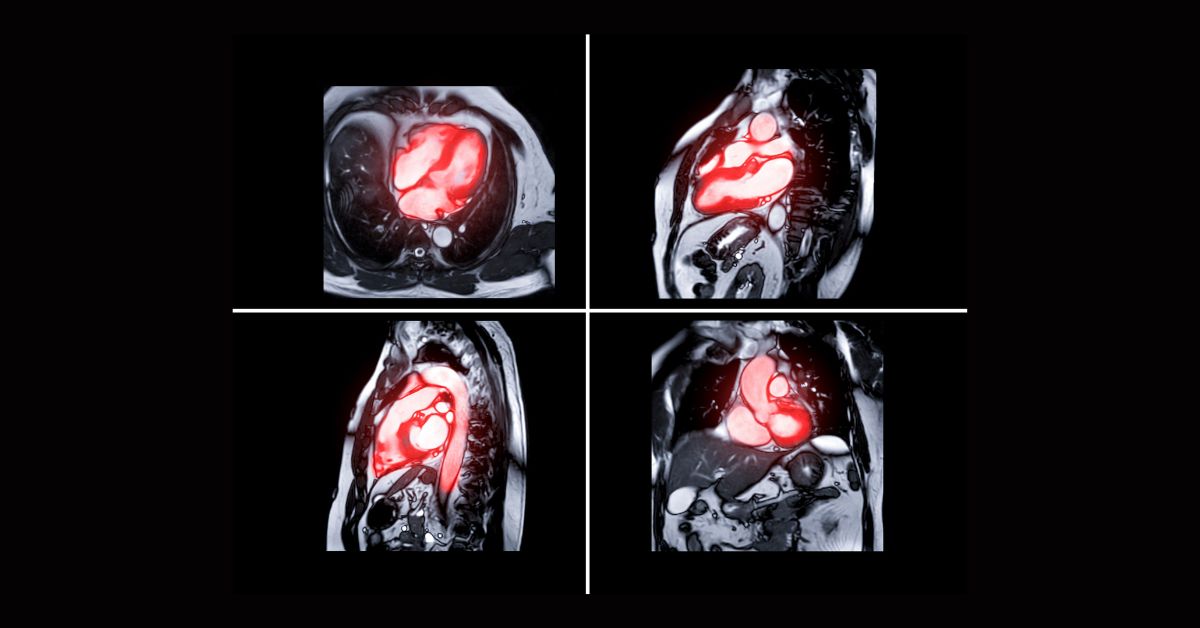

La RM cardiaca trova applicazione nello studio della cardiopatia ischemica, delle valvulopatie, delle cardiomiopatie e delle malattie del pericardio, oltre che delle cardiopatie congenite e delle masse.